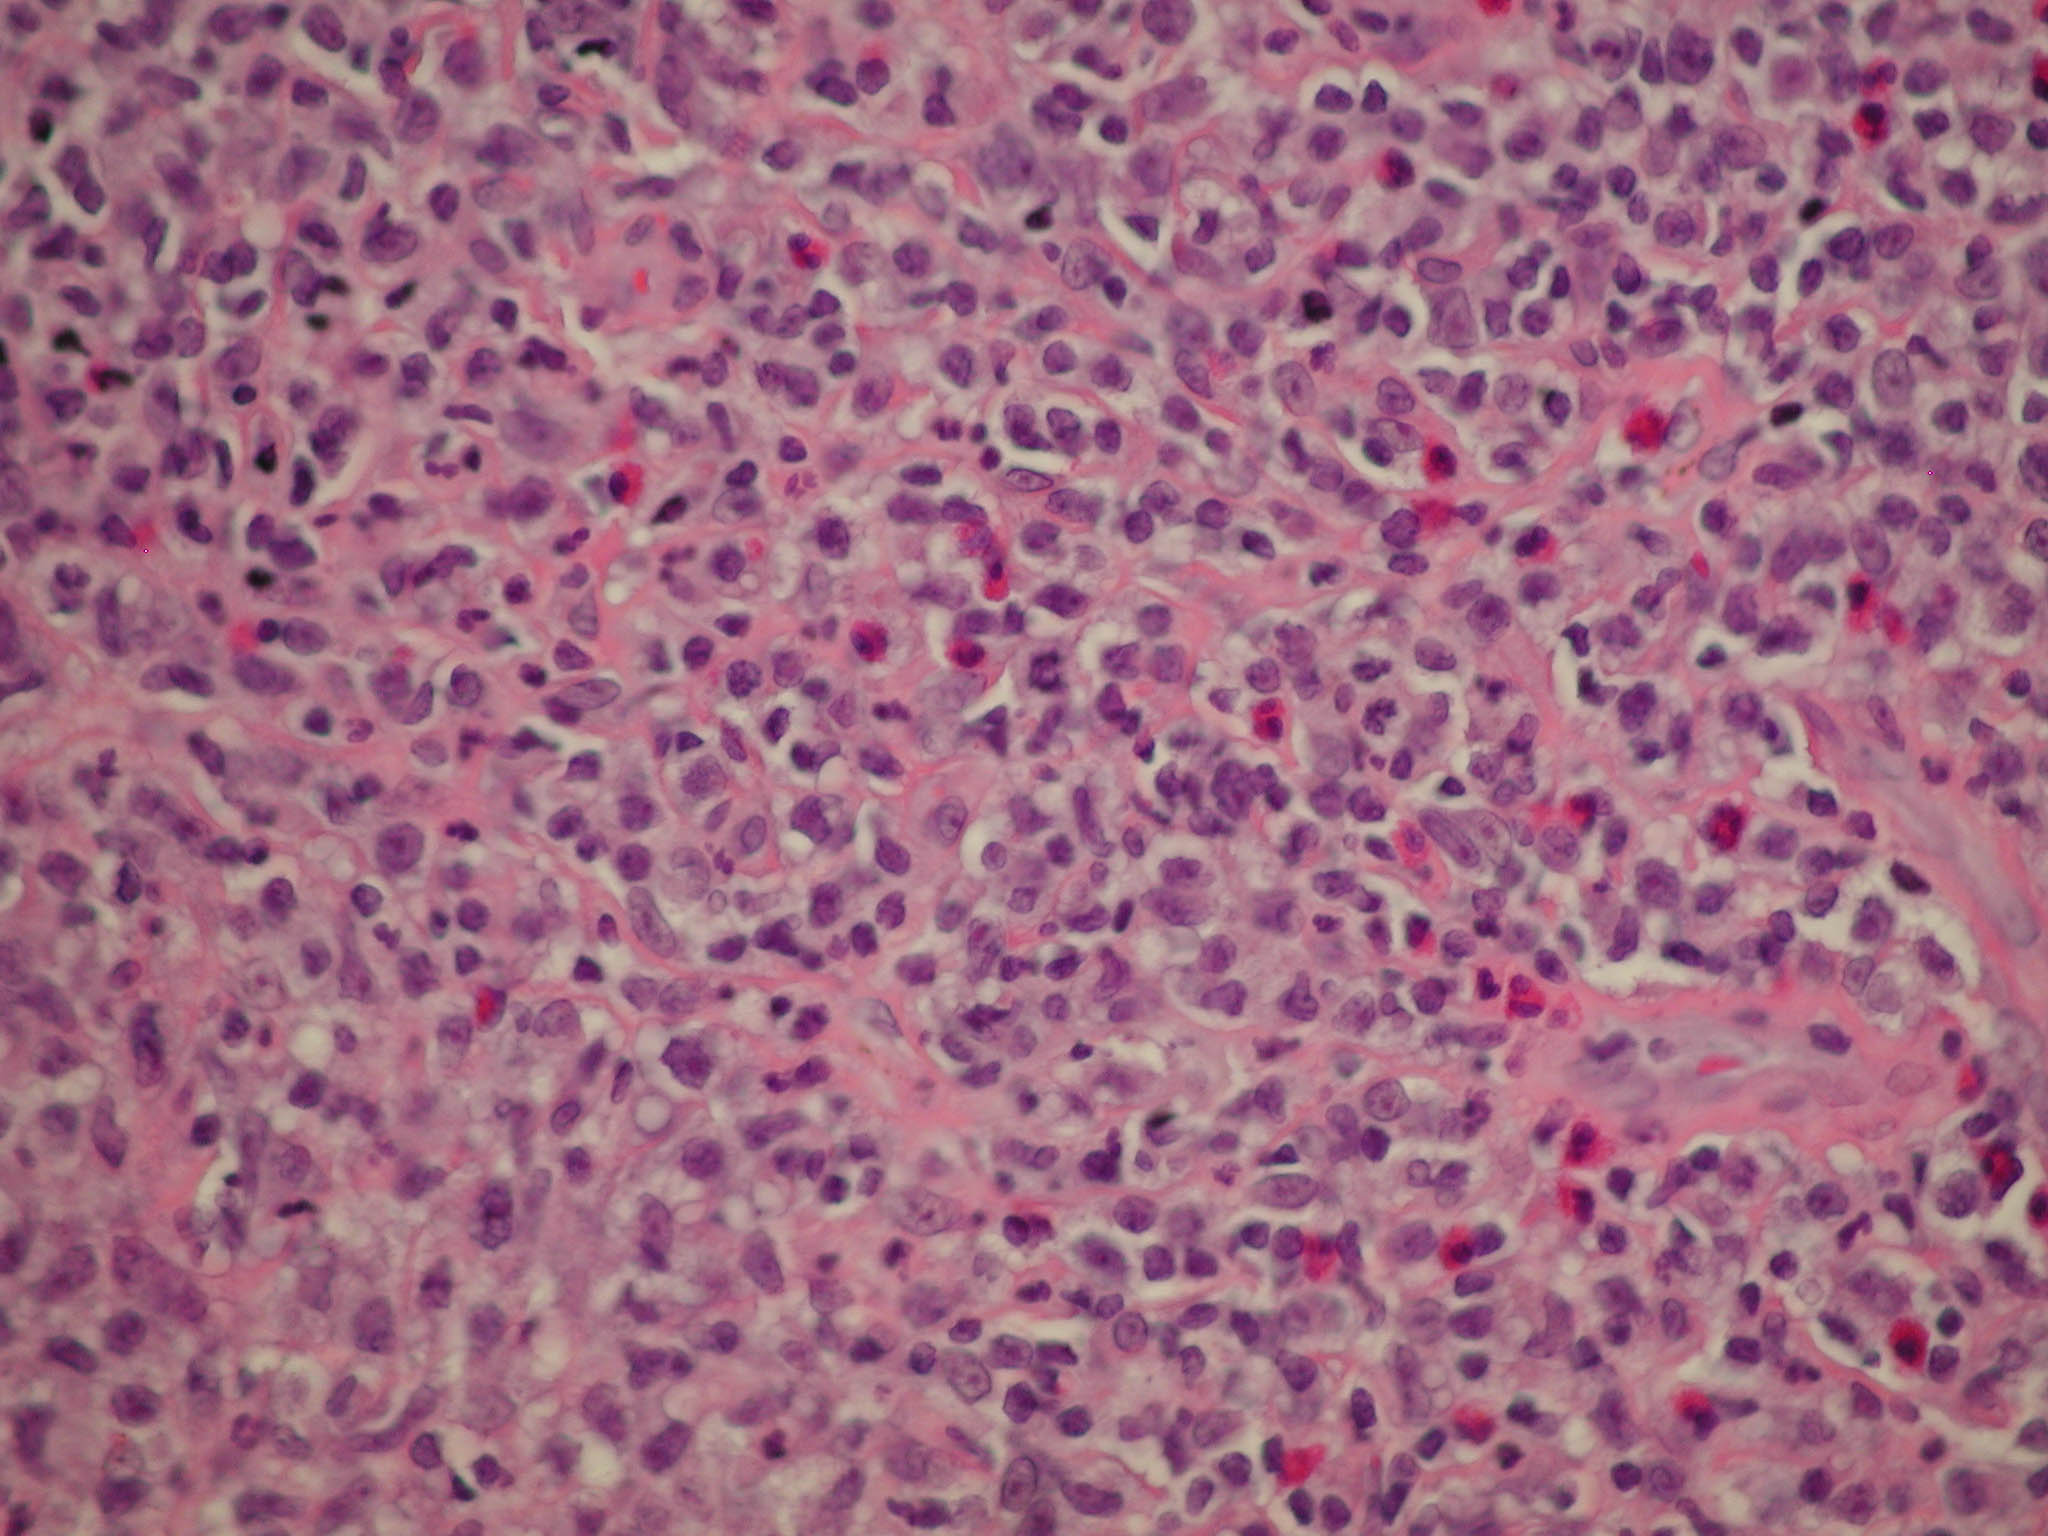

Mycosis Fongoïde =التفطر الكمئي